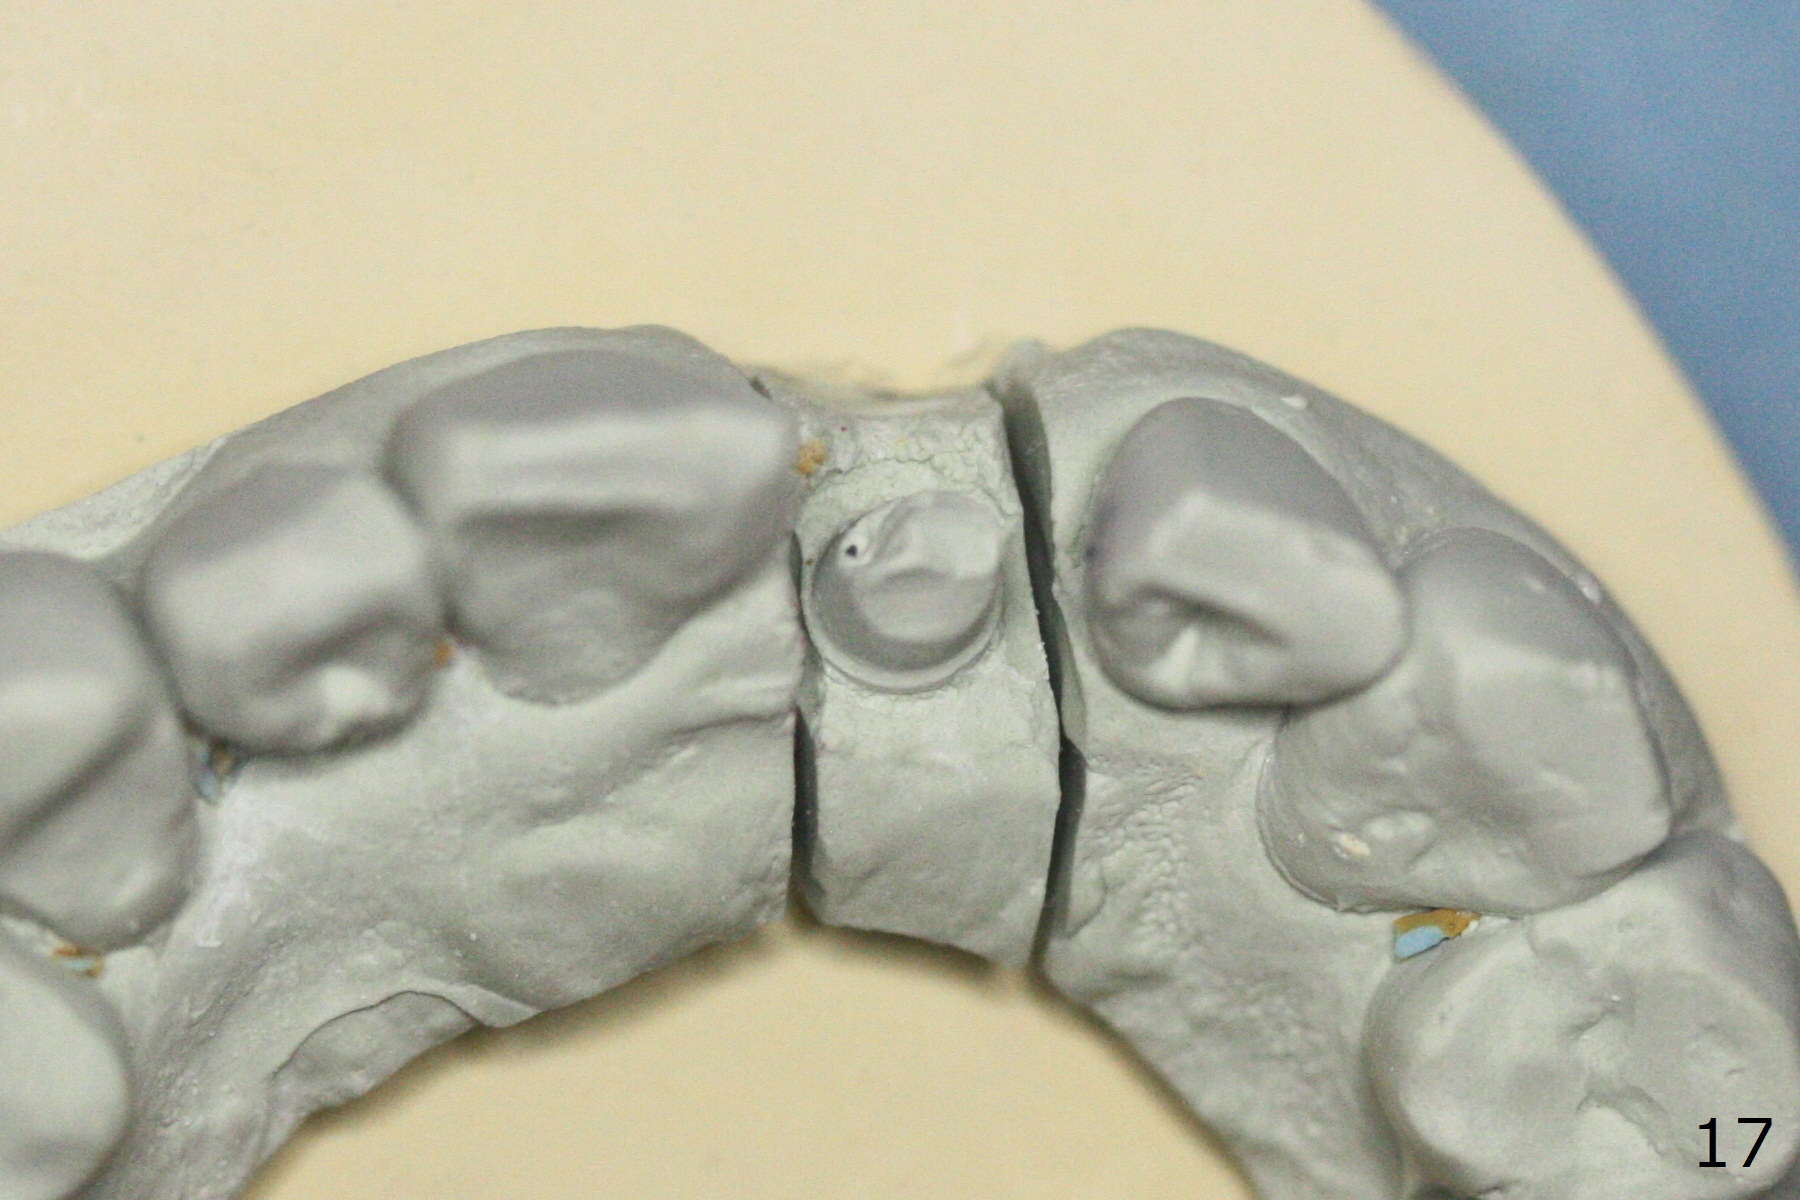

Limited Ortho with Proximal

Reduction

Nearly 7 months postop, the immediate provisional at UL1 is removed; with the mesial reduction of UL2 from 7 to 6 mm (Fig.1), an angled abutment is to be changed (4.5x15 degree, 2 mm cuff). A new provisional (Fig.2,3) co-incides with the facial midline. Brackets will be placed between UR4 to UL3 except UL2 (symptomatic once with chronic periodontitis) with initial proximal reduction between UR1-4 in preparation to correct cross bite of UR2. Twelve days later, the patient returns for UR5-UL3 bracketing after UR1-4 initial proximal reduction with 14 niti wire (Fig.4-6). UR1 moves mesial 20 days post open coil spring (Fig.7 arrow), while UL1 debracketes after permanent re-cementation of the temporary crown last visit (*, no re-bracketing, since it appears not essential). Before placement of 20 ss wire, diastemata are created by proximal reduction (Fig.8 *). In fact UR1 moves mesial, while UR3 does not move distal with the open coil. With placement of UR6 (implant) molar band, UR3 is distalized effectively. With sling shot, UR2 is almost labialized in one appointment (Fig.9). After consolidation of the diastemata between UR1-6 with power chains following UR2 cross bite correction (Fig.10), the restoration space for UL1 seems to be too large (Fig.11). Next visit, check the midlines, take 1-2 PAs for #7-9 and determine whether a straight abutment should be changed back and whether composite should be placed UR1 mesial to reduce the space. One week later, composite is added to the mesial surface of the tooth #8 to increase its width, while the provisional at #9 is relined to improve the interdental papilla (Fig.12). Minimal bone loss at UR2 is observed 8 months post banding (Fig.13), while the socket at UL1 seems to have healed except the most coronal 1 year 3 months postop (Fig.14 *). The margin of the abutment should be uneven, more coronal proximal than buccopalatal (Fig.15). The final crown has an open margin, partially due to less ideal trajectory (Fig.16 (black line: ideal trajectory, nearly 1 year 4 months postop)). Guided surgery could solve the problem. Sticky bone may restore the buccal plate defect. Die shows that the implant is palatally placed (Fig.17). CT will be taken to determine whether the implant perforates the palatal plate.